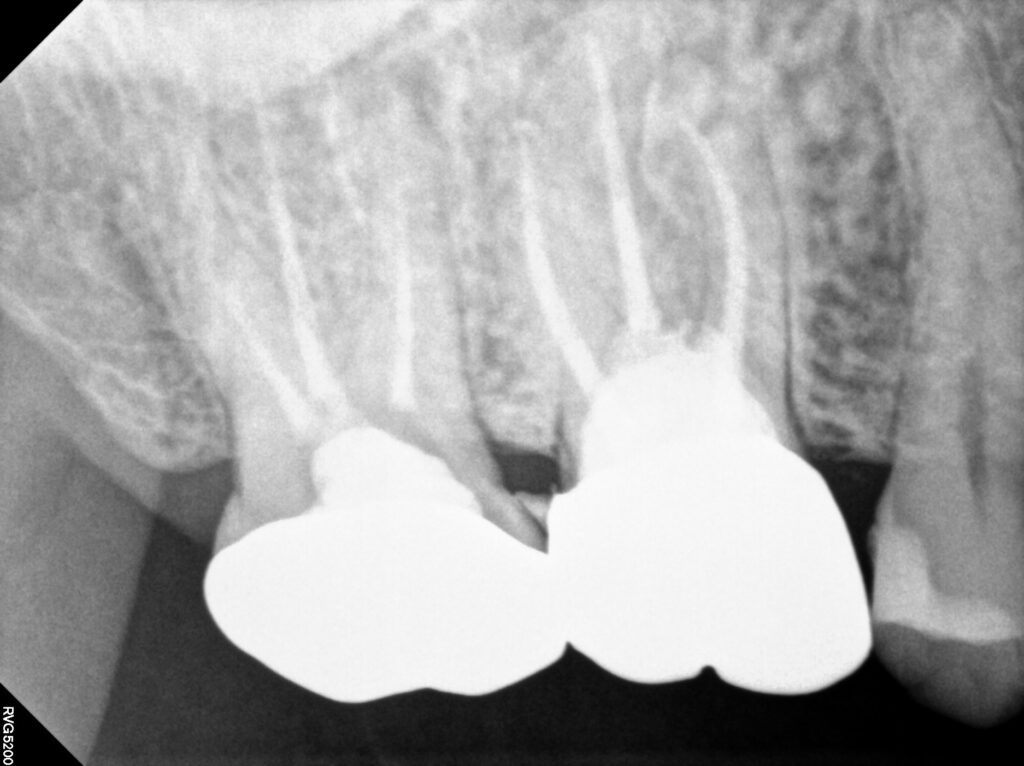

환자분께서는 오른쪽 위 크라운을 씌운

어금니에 염증과 통증이 생겨 치아가

흔들리신다며 광화문치과에 내원해 주셨는데요.

오른쪽 위 첫번째 어금니 치아 뿌리 염증으로 인해

잇몸이 부어 고름 주머니가 형성된 것을

확인할 수 있었는데요.

남아 있는 치질의 양이 적고

예후가 좋지 않을 수 있지만

임플란트 식립을 염두에 두고

기존의 크라운을 제거해보기로 하였습니다.

역시 남은 치질이 많이 없었는데요.

치아의 테두리는 남아 있어

재신경치료를 진행하였고

염증과 고름주머니, 통증이 사라져

단단한 재료로 메워 크라운을 진행하도록

준비하였습니다.